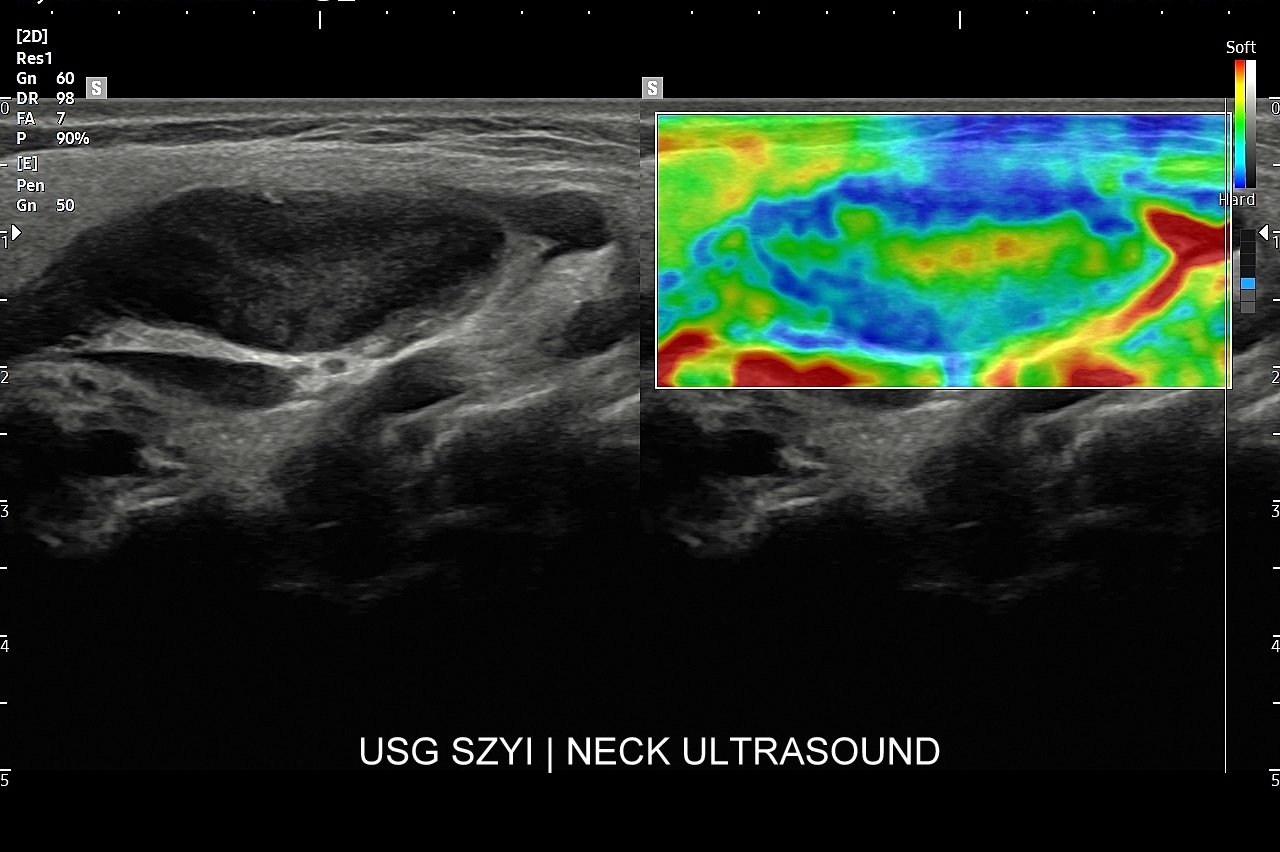

W Interdyscyplinarnej Pracowni USG dr Tomasza Szczepańskiego istnieje możliwość przeprowadzenia wysokospecjalistycznej oceny gruczołu tarczowego w postaci multiparametrycznego badania MPUS tarczycy, które wykonywane jest na zaawansowanym technologicznie aparacie USG przy wykorzystaniu modalności zwiększających rozdzielczość obrazowania zmian chorobowych oraz wnoszących istotne, dodatkowe dane kliniczne dotyczące zmian patologicznych w organie. Badanie MPUS tarczycy jest szczególnie przydatne w przypadku diagnostyki i oceny guzków tarczycy oraz ich kwalifikacji do dalszego postępowania. Nowoczesne modalności MPUS, o których mowa, obejmują w szczególności badanie dopplerowskie miąższu gruczołu, ocenę dopplerowską tętnic tarczycowych, badanie mikroprzepływów  MVF oraz elastografię.

Czy przy USG tarczycy wykonywana jest elastografia? W przypadku stwierdzenia w gruczole stanów patologicznych, np. guzków, a posiadając przy tym aparat USG dysponujący elastografią, można zastosować tenże tryb w celu uzyskania dodatkowych danych medycznych dotyczących wykazanego guzka. Poza elastografią tarczycy ważniejszym dodatkowym trybem obrazowania guzków tarczycy jest tryb mikrounaczynienia MVI.